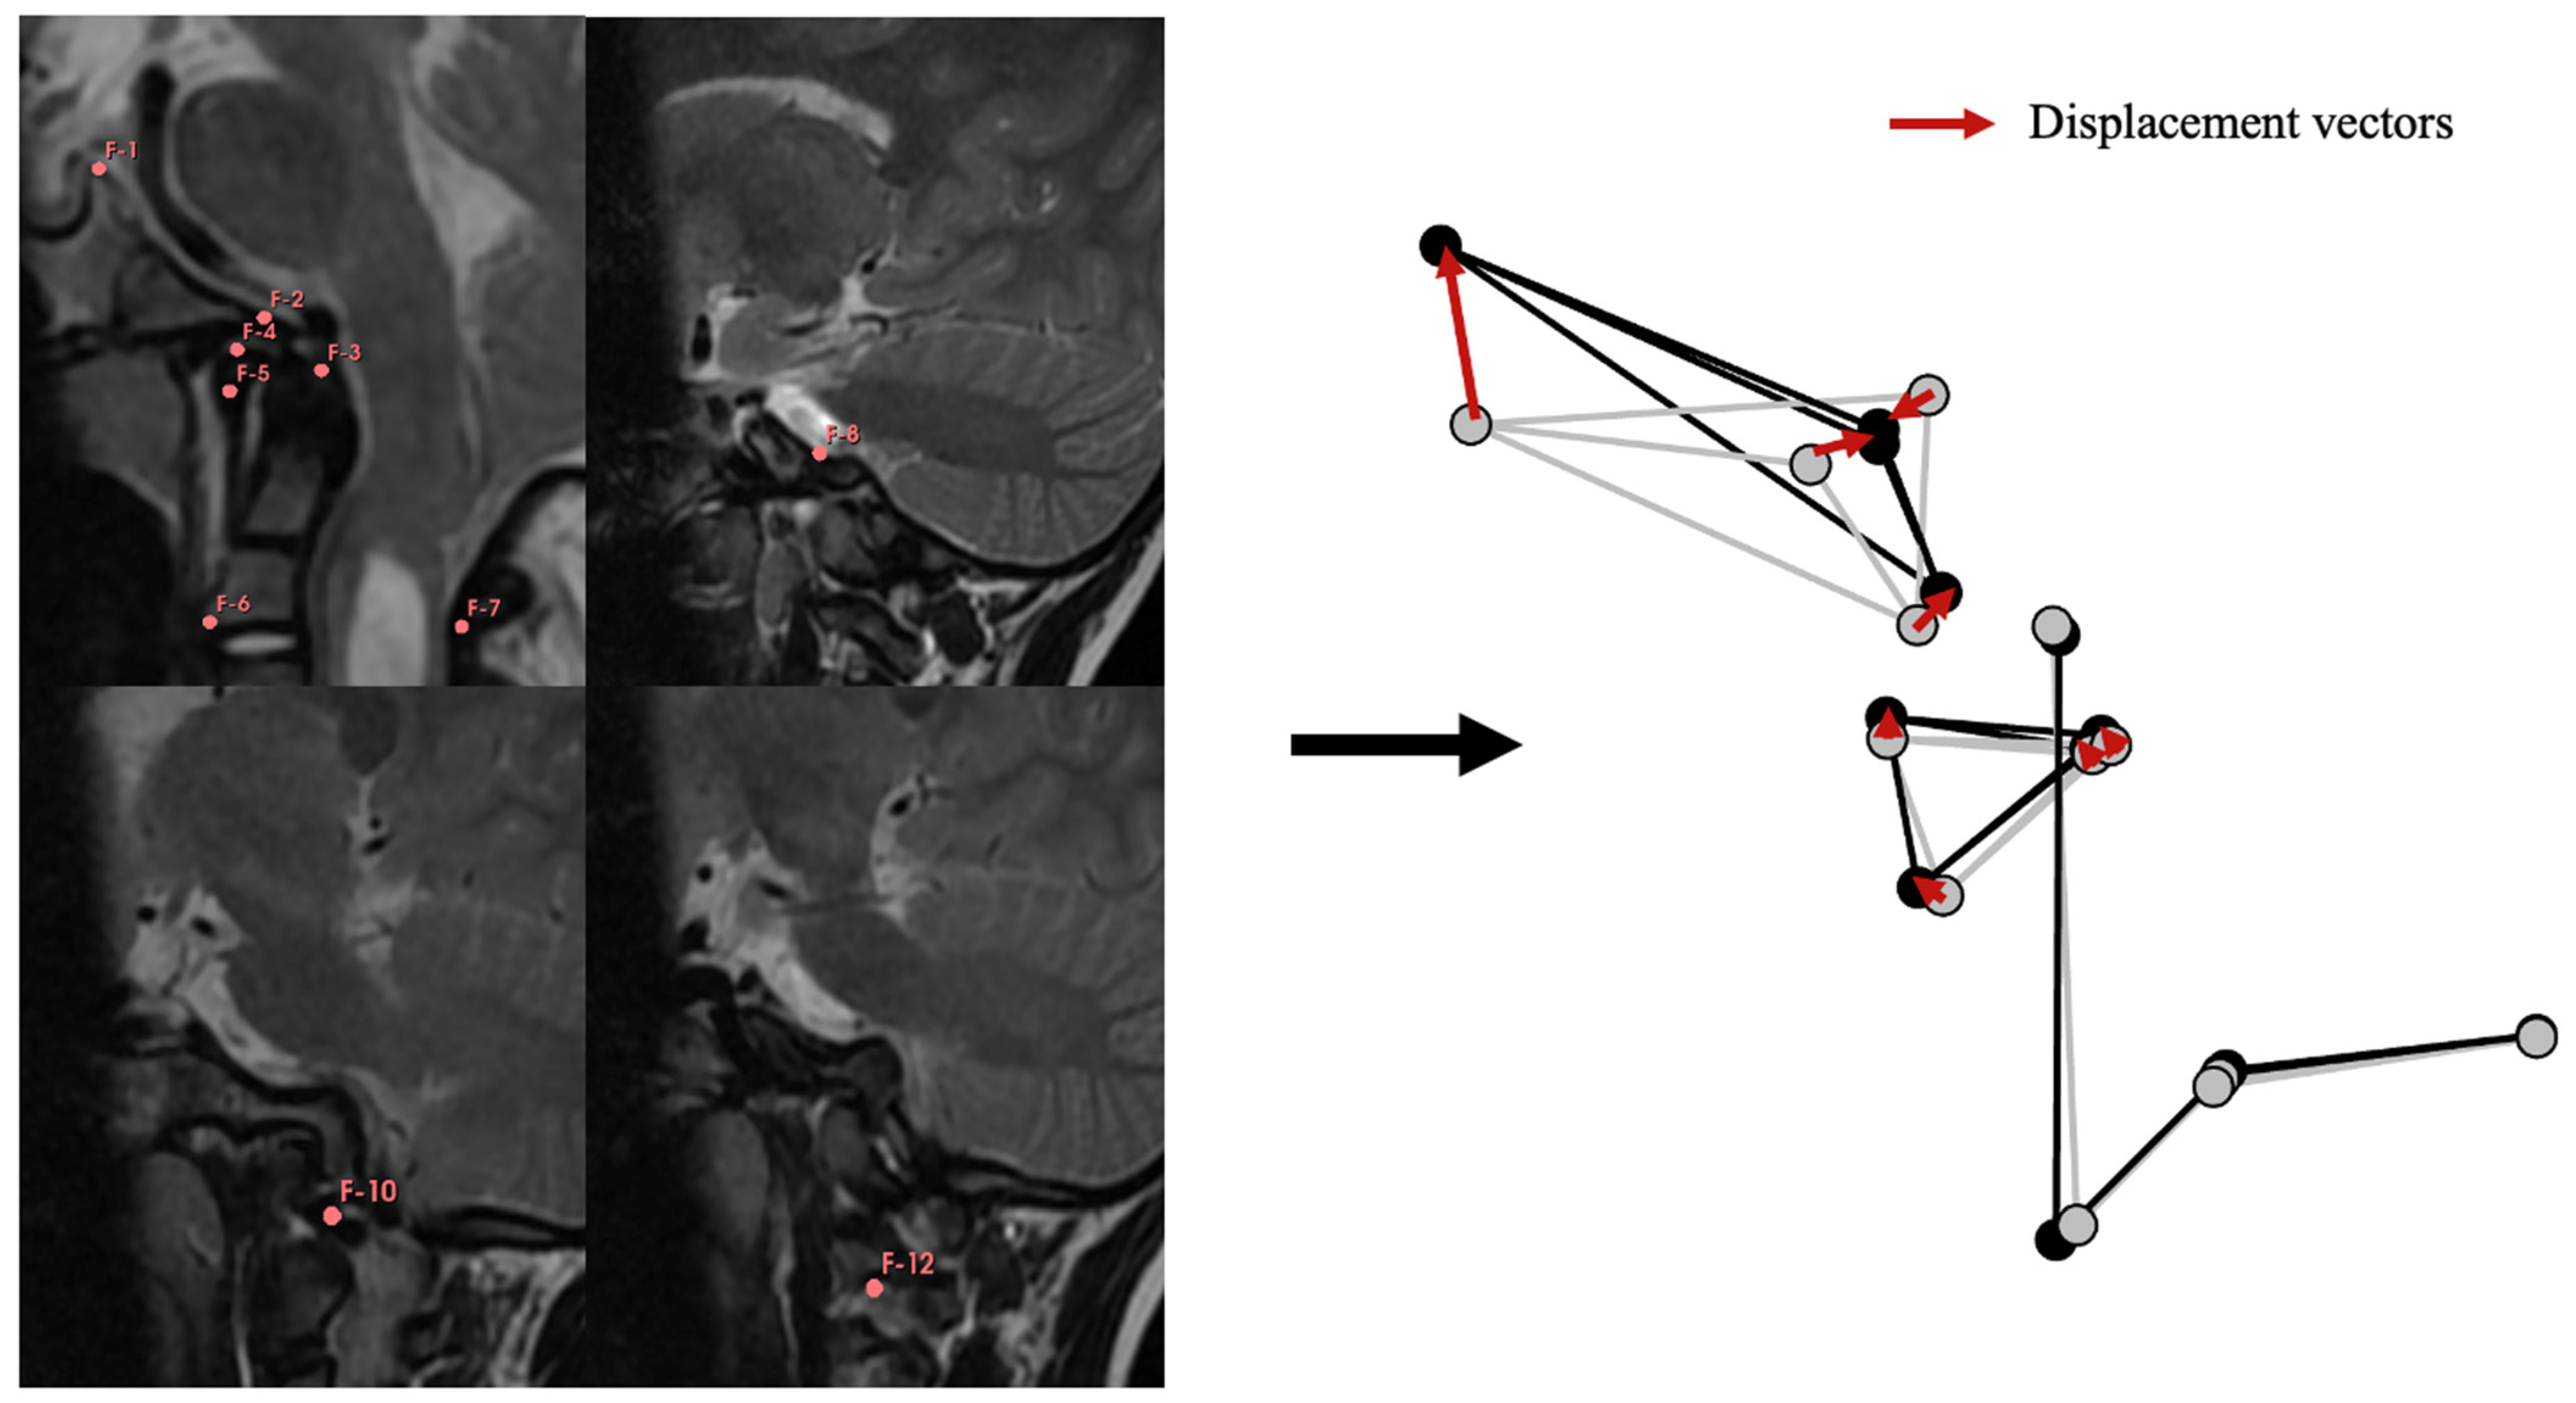

The initial phase involved the creation of a geometric model of the CVJ to assess the mobility of the bony elements based on the three-dimensional position of reference points. All mMRIs were imported into 3D Slicer v. 5.0.3. Using the segmentation tool, thirteen reference points, or landmarks, were positioned on the CVJ in a specific anatomical sequence (Figure 1) for each mMRI in flexion and extension positions. Inter-observer measurements were estimated and controlled by repeating measurements five times in one patient in the neutral, flexion, and extension positions. Intra-observer measurements were obtained by repeating measurements five times in three patients for each position. Cartesian coordinates (x, y, and z) were extracted for each reference point, and the package “morpho” in R was used to standardize the position, orientation, and size of all configurations by computing a Generalized Procrustes Analysis (GPA, using the function “ProcSym”). All subsequent analyses were based on these standardized Procrustes coordinates. The GPA aligned the landmarks corresponding to C2, meaning that C2 will be considered fixed at all times to capture the mobility of C1 and the cranial base. The displacement vectors were calculated for each landmark of C1 and cranial base in every patient to account for the bone displacements between the flexion and extension positions (Figure 1).

Figure 1.

Geometric modeling of the CVJ. Reference points were positioned in the same order for each patient in each position (flexion, neutral and extension), as follows: F-1: Dorsum sellae; F-2: Basion; F-3: Tip of the dens; F-4: Antero-superior arch of C1; F-5: Antero-inferior arch of C1; F-6: Antero-inferior part of C2 body; F-7: Antero-inferior part of C2 lame; F-8: Left antero-medial part of jugular foramen; F-9 not shown but symmetric to F-8 on the right side; F-10: Left insertion site of transverse ligament; F-11: not shown but symmetric to F-10 on the right side; F-12: Left antero-supero-medial part of C2 intervertebral foramen; F-13: not shown but symmetric to F-12 on the right side. Geometric model on the right side: Flexion position shown in light grey, extension position shown in black. Using these models, “bone displacements” were calculated, represented as displacement vectors between the flexion and extension positions for each reference point (red arrows).